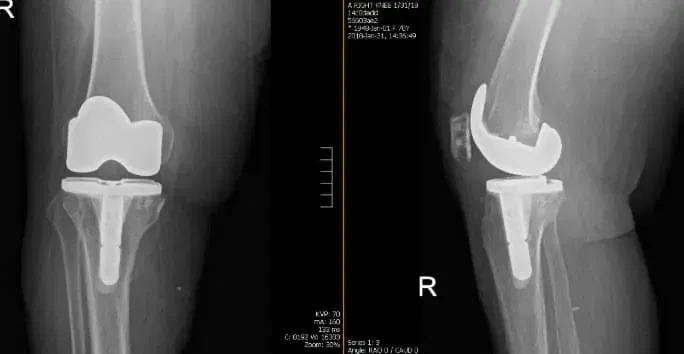

Patient underwent a Right Total Knee Arthroplasty. Postoperative films revealed normal bony texture. No destructive abnormalities, fracture or dislocation are present. Patient is a status post-right-sided arthroplasty with satisfactory position of the hardware Patient feels optimal relief and only required the standard outpatient postoperative physical therapy services. Range of motion and weight bearing are satisfactory.

Tibial tray with stem

The tibial stem as shown in the image above allows better stabilization and transmission of forces acting on the joint distally, thus reducing wear and tear of the polyethylene insert.